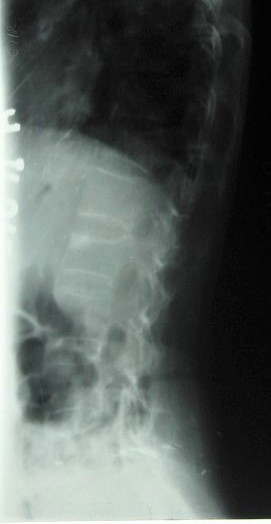

A S Romanus sign 3

Lumbar Spine Lateral view – another patient